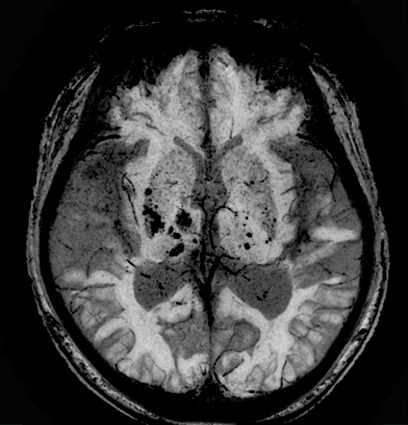

磁化率強調画像であるFSBBでは、MPGパルスの印加強度を位相・周波数・スライス方向など別々に制御可能とし、さらに、位相画像を用いた強調処理や位相画像のみの出力も可能とした。これにより、細かな血管や磁化率の変化をより詳細に捉えることができる(図1)。